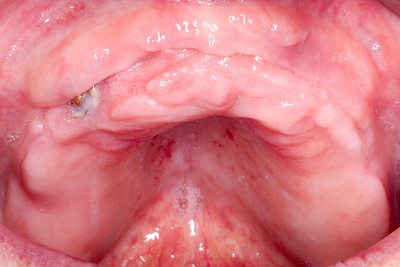

Schwellung ohne Eiter: faltenförmig

Als Sonderform des Reizfibroms können bei Zahnprothesen in den Randbereichen selten am Gaumen, häufiger außen in den Umschlagfalten in Ober- und Unterkiefer auch lappenartige Auffaltungen (Lappenfibrome) beobachtet werden, die ebenfalls aufgrund eines mechanischen Dauerreizes entstehen. Alle diese Veränderungen sind in der Regel eher wenig schmerzhaft – auch wenn man darauf drückt. Hier sollte zeitnah mit einem Zahnarzt eine Abklärung erfolgen.